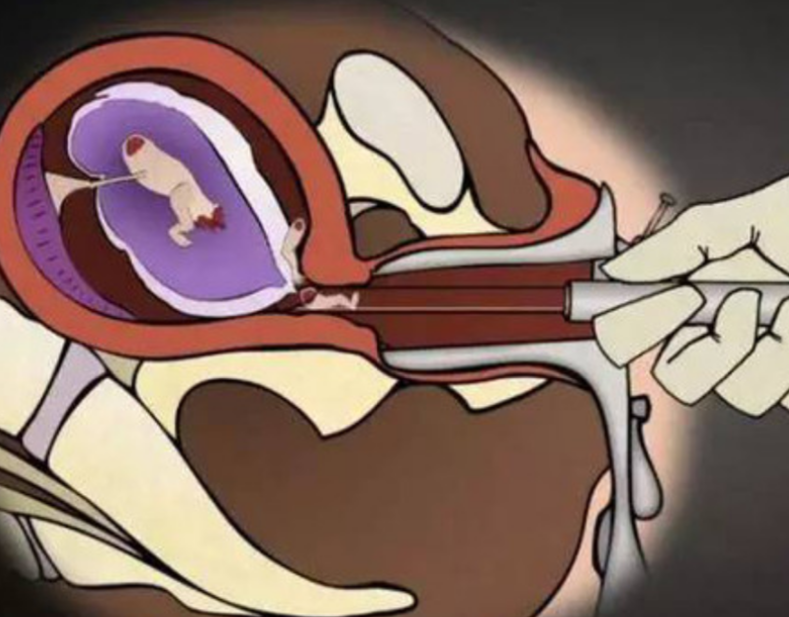

正在治療的人工陰道

治療中的人工陰道的

治療中的人工陰道

人工陰道治療

人工陰道治療前期

人工陰道治療前後